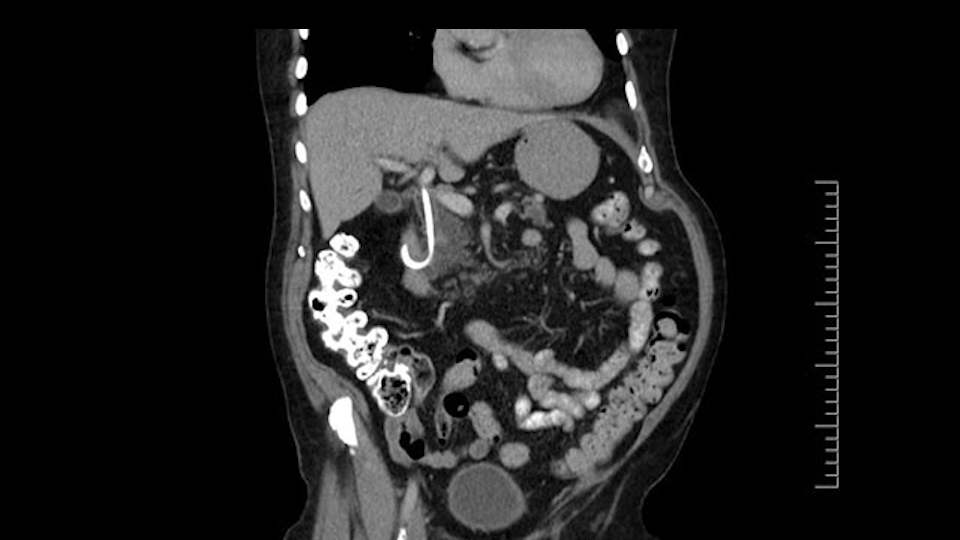

The next item that I would look at: the issue would be the vessels and usually start at the portal vein, watch the portal vein, follow it down, down-down-down to the neck of the pancreas - which is here - and there’s no impingement by tumor, which is great. The SMV and the splenic vein, which is here. The splenic vein junction is normal, which is great.

Then look at the first jejunal branch - which is this thing here - this little branch which goes under the SMA. It’s something that we’ve just started appreciating over the past few years and the reason for that is: there’s two or three small branches that come out of the uncinate into the the first jejunal and it’s a fairly inevitable part of the operation where there’s some bleeding. As long as you’re cognizant of what’s happening, it’s no reason to panic and that kind of bleeding will eventually stop or can be stopped but it’s not easy because these little vessels are fragile from the uncinate to the first jejunal. So I do focus on that and it’s pretty consistent I’d say 9 times out of 10, people have that first jejunal.

The other thing I look at is the gastroepeiploic arcade- which is this thing here- which is where the gastroepeiploic vein joins the portal vein. I call it the gateway to the neck of the pancreas because you pretty much have to divide it to get to the neck. The middle colic vein usually drains either into it or nearby. I think we’re seeing it here. Again,that can be divided and I usually divide those two and it helps me get under the neck. Again, there’s no issues here with the tumor so it’s nice from that perspective. If I was concerned about the vein, which I’m not here, I would go to the coronal view. It’s a nice way to look at the vein on just a couple of cuts and you can see a beautiful view of it here. There’s the portal vein, there’s the head of the pancreas. There’s the tumor. It’s a little closer here than it looks on the other one. I doubt it’s involved. If it’s touching, it may not be invading it but even if it was, it's a short segment. Anyways, there’s the SMV there’s the splenic vein, and everything looks good. You can see the stent. I ignore the stent. It’s the most dramatic looking thing in the picture but it’s actually the least important.

The next thing we always evaluate, although we do not expect invasion to the portal veins in this case, we must always trace the path of the portal vein, in both directions, from top to bottom. The splenoportal confluence and the superior mesenteric vein, which in this case does not appear to be compromised.

Por otro lado, siempre evaluamos -aunque en este caso no esperamos que haya invasión de los vasos portales-, siempre hay que hacer el recorrido de la vena porta, en ambos sentidos, de arriba hacia abajo; el confluente esplenoportal y la vena mesentérica superior, que en este caso no aparentan estar comprometidos.